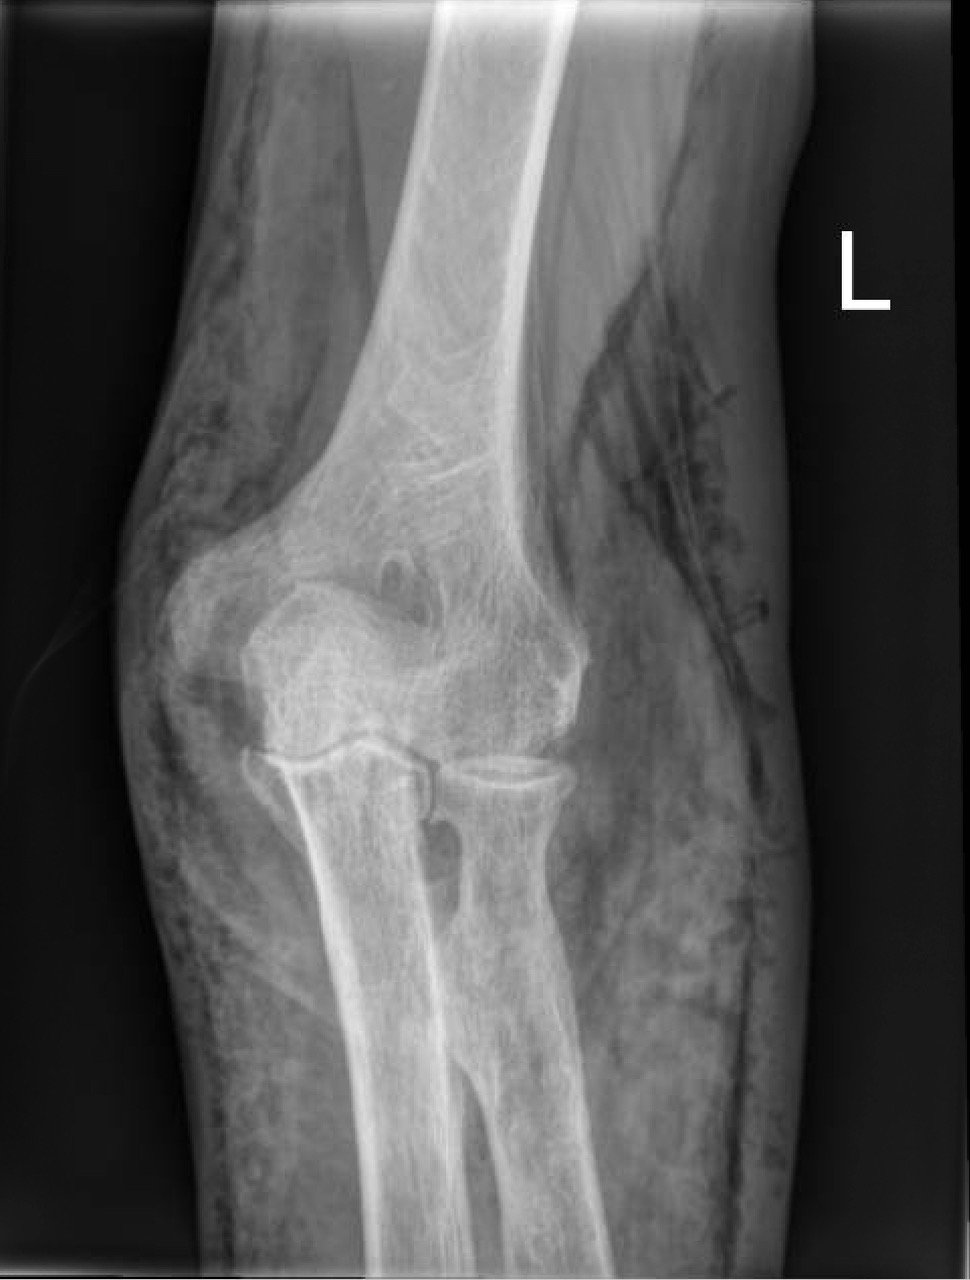

X-Rays of the elbow revealed diffuse striated lucencies throughout the soft tissue, consistent with extensive subcutaneous air throughout the superficial and deep tissues. There was no evidence of a fracture.